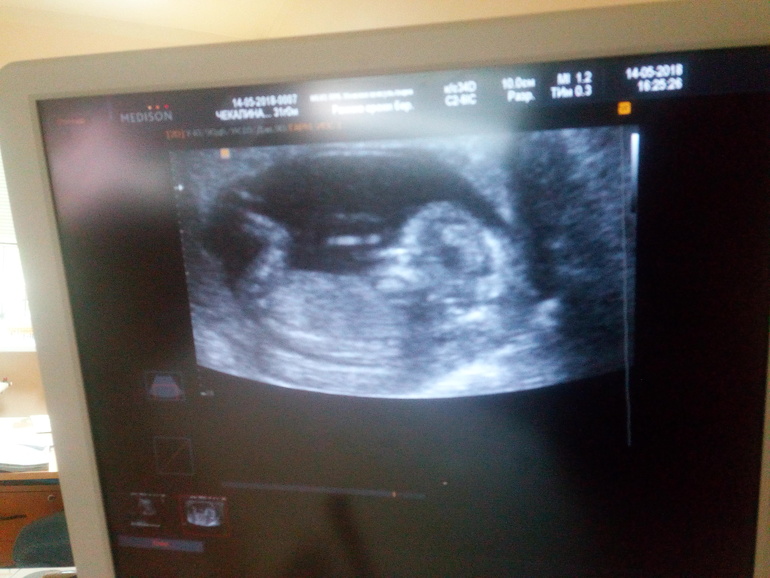

Привет! Еду со второго скрининга и не могу успакоиться. Уже рот болит от улыбки! У меня будет дочка!!!

С чего начинается Счастье?

С полосок на тесте твоём,

С УЗИ что сердечко покажет,

С того, что теперь вы вдвоём...